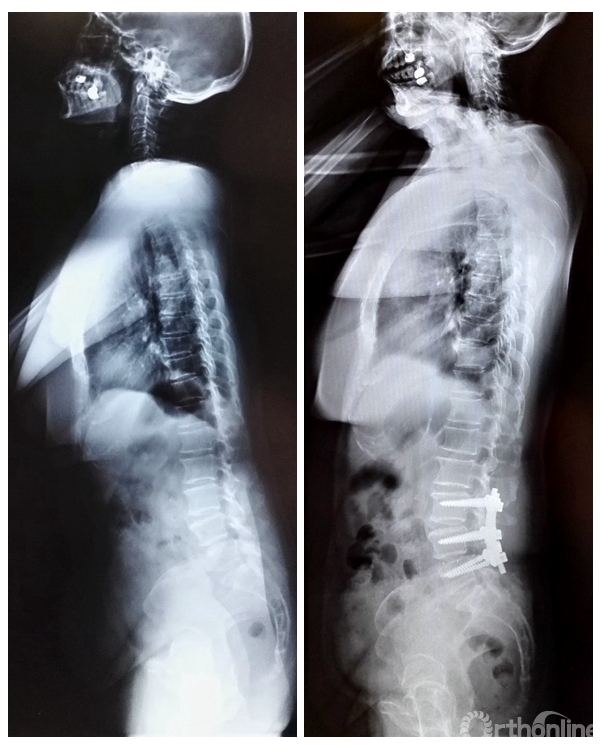

76岁女性,诊断腰椎管狭窄症(L3-5),术前矢状位参数SVA=12cm,LL=22°, PI=55°,PT=24°,TK=5°,脊柱矢状位S型曲线消失,近似直线。行L3-5椎管减压PLF术,术后1月复查矢状位参数SVA=-0.4cm,LL=45°, PI=58°,PT=22°,TK=10°,较术前明显改善